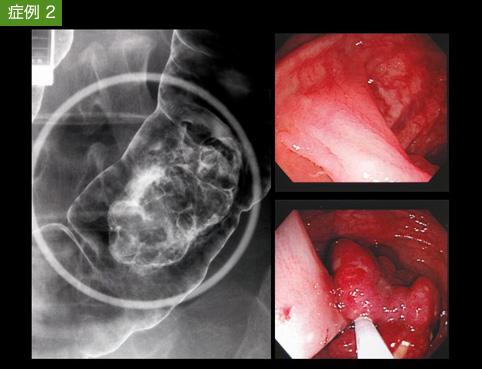

Two cases of hamartomatous polyp (Peutz-Jeghers type polyp) with a long stalk in the colon.

Saga Pref., Saga Prefectural Hospital KOSEIKAN (Dr.Takahashi & Dr.Shimoda)

Tumor-like lesions/Others

Large intestine(Colon)/Transverse colon

X-ray

25 - 29